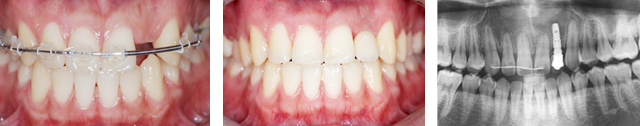

오른쪽 앞니 상실로 내원한 환자분. 앞니의 상실로 치아 사이 틈이 넓어지고 있어 교정으로 임플란트 식립 공간을 만든 후 임플란트 식립을 하였습니다. 앞니가 상실된 기간이 길어 교정치료를 하지 않고 임플란트를 식립할 경우 벌어진 치아 사이로 음식물이 끼거나 치아형태 이상으로 문제가 생길 수 있습니다.